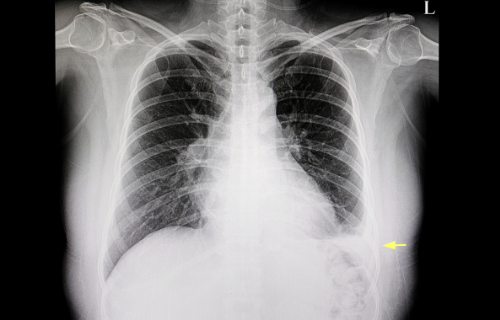

Pericardial effusion occurs when there is excess fluid in the pericardium, a tough and double-layered saclike structure surrounding the heart. There are usually two to three tablespoons of clear yellow fluid that helps the heart move easier within the sac. However, an individual with pericardial effusion may have 100 ml to more than 2L of fluid between the sac’s two layers (Hoffman, 2020).

One of the most common causes is pericarditis, more fluid is produced due to the inflammation of the sac. The inflammation is usually caused by viral infections such as HIV, lupus, tuberculosis, echoviruses, cytomegalovirus, and coxsackieviruses. Other causes include cancer, heart injury due to medical procedure, heart attack, kidney failure, and autoimmune diseases. In many cases, a specific cause could not be found, and the condition may be called idiopathic pericardial effusion (Hoffman, 2020).

The treatments may include medication (antibiotics and pain relievers), pericardiocentesis (draining the fluid), and surgery (Kang, & Wojcik 2021).